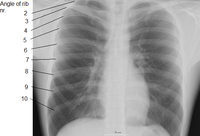

Variations in the number of ribs occur. About 1 in 200-500 people have an additional cervical rib, and there is a female predominance.[7] Intrathoracic supernumerary ribs are extremely rare.[8] Bifid or bifurcated ribs, in which the sternal end of the rib is cleaved in two, is a congenital abnormality occurring in about 1.2% of the population. The rib remnant of the 7th cervical vertebra on one or both sides is occasionally replaced by a free extra rib called a cervical rib, which can mechanically interfere with the nerves (brachial plexus) going to the arm.

Rib fractures are the most common injury to the rib cage. These most frequently affect the middle ribs. When several ribs are injured, this can result in a flail chest which is a life-threatening condition.

Abnormalities of the rib cage include pectus excavatum ("sunken chest") and pectus carinatum ("pigeon chest").